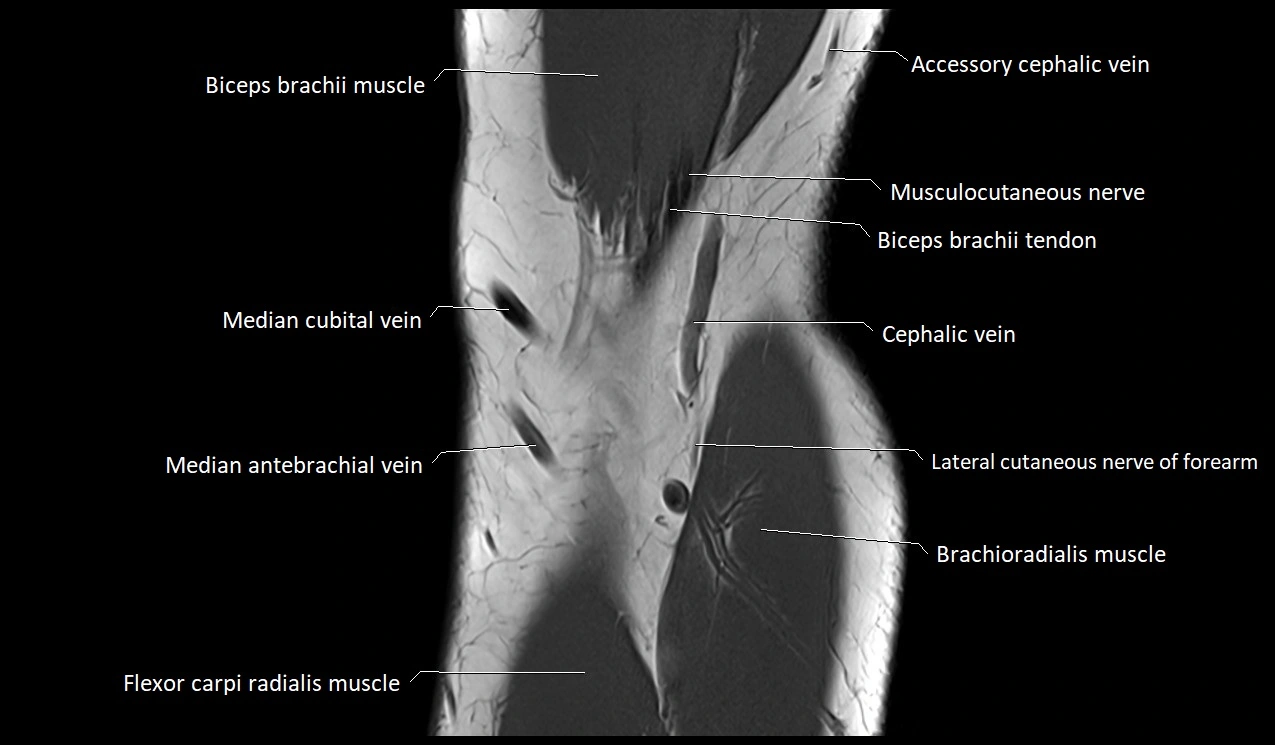

Accessory cephalic vein

The accessory cephalic vein is a variable superficial vein of the upper limb, typically draining the lateral and posterior aspects of the forearm and joining the cephalic vein near the cubital fossa or distal arm. It provides an important collateral drainage pathway for superficial venous return of the forearm.

It is often used as a landmark during venipuncture, vascular access creation (AV fistula), and venous graft harvesting. Due to its variable anatomy, precise imaging evaluation is essential before surgical or interventional procedures.

Origin, Course, and Termination

• Origin: Arises from the dorsal venous network of the hand, often from the lateral side of the dorsal venous arch.

• Course:

• Ascends along the lateral aspect of the forearm, anterior to the brachioradialis muscle.

• In the distal or mid-forearm, it may communicate with the median cubital vein or directly with the cephalic vein.

• Continues proximally on the radial border of the forearm and sometimes runs superficial to the lateral cutaneous nerve.

• Termination:

• Joins the cephalic vein just below or in the region of the cubital fossa; occasionally drains higher into the arm or shoulder region.

Relations

• Anteriorly: Superficial fascia and skin of the lateral forearm

• Posteriorly: Brachioradialis muscle and lateral antebrachial cutaneous nerve

• Medially: Communicating veins from the dorsal venous network or cephalic vein

• Laterally: Radial artery (deep), separated by fascia